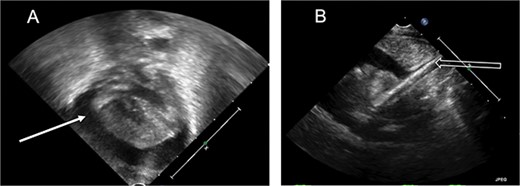

At our institution, the patient underwent venoarterial (VA) ECMO cannulation on day of life 1, with a 12 French (Fr) venous cannula in the internal jugular vein and an 8 Fr arterial cannula in the carotid artery. Over the next 24 h, she became intermittently hypotensive, to a mean arterial pressure of 20–30 mmHg, and tachycardic, above 200 beats per minute, with decreasing ECMO flows. Despite resuscitation with blood products, she remained hemodynamically unstable with persistently low ECMO flows. Cardiac tamponade was suspected, and echocardiogram confirmed a large pericardial effusion with severely diminished biventricular systolic function (Fig. 1). With concern for possible cardiovascular perforation during ECMO cannulation, she was taken emergently for mediastinal exploration. A pericardial window was performed with drainage of 20 ml of opaque, milky fluid and immediate improvement in ECMO flows. No signs of cardiac injury, vascular perforation or hemorrhage were observed. Fluid analysis was sent (Table 1) and a right pleuro-pericardial window was created, with a 15 Fr drain placed.

Echocardiogram. (A) Apical view, pericardial effusion (white solid arrow). (B) Subcostal view, ECMO catheter tip seen entering the right atrium (white hollow arrow).